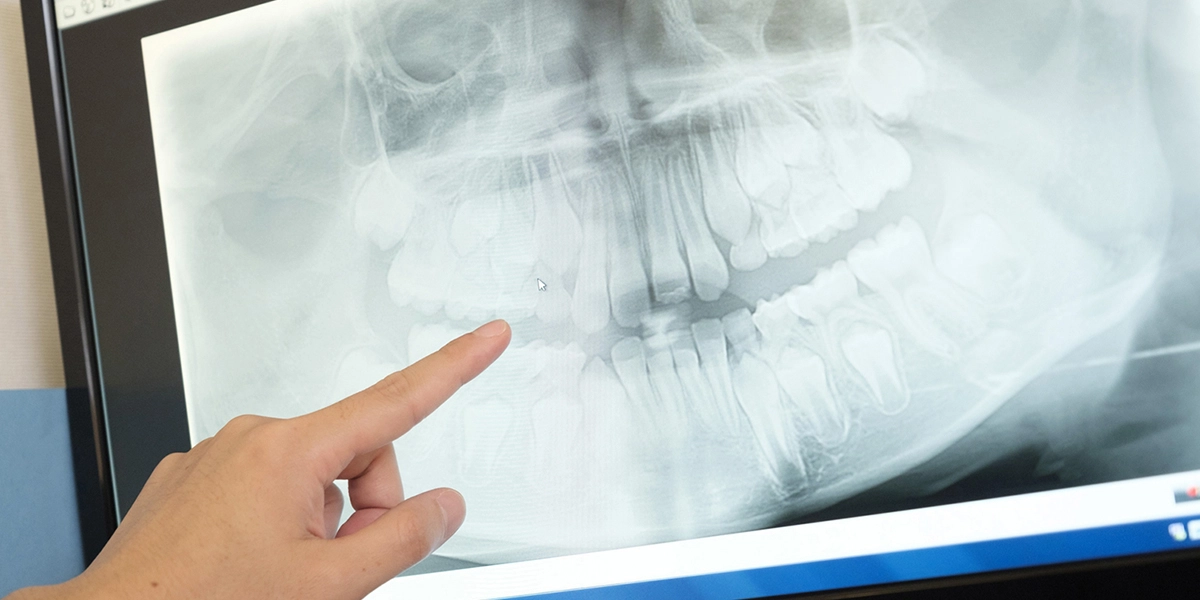

- 複雑な根の形や数、病変の広がりを確認するための歯科用CTの活用

精密な治療を行うための設備として、歯科用CTと歯科用顕微鏡を導入しております。

①診査・診断

問診・温度診・電気診・触診・圧痛の有無・レントゲン撮影により根管治療の必要があるか判断します。レントゲン撮影は根管治療をする上で診断に必要です。また虫歯の大きさ、病変の広がり、根の形態や数を知るためにも必要です。

根管の形態は非常に複雑で通常のレントゲンのような二次元画像で診断が難しい場合があります。そのため当院では歯科用CTを用い診断に役立てています。また通常の根管治療で治癒しなかった場合、十分に清掃できない部分を切断し、特殊なセメントで感染を遮断する外科的歯内療法を行います。